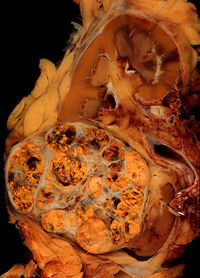

Cancer (medical term: malignant neoplasm) is a class of diseases in which a group of cells display uncontrolled growth ( division beyond the normal limits), invasion (intrusion on and destruction of adjacent tissues), and sometimes metastasis (spread to other locations in the body via lymph or blood). These three malignant properties of cancers differentiate them from benign tumors, which are self-limited, do not invade or metastasize. Most cancers form a tumor but some, like leukemia, do not. The branch of medicine concerned with the study, diagnosis, treatment, and prevention of cancer is oncology.

Hippocrates described several kinds of cancers. He called benign tumours oncos, Greek for swelling, and malignant tumours carcinos, Greek for crab or crayfish. This name comes from the appearance of the cut surface of a solid malignant tumour, with the veins stretched on all sides as the animal the crab has its feet, whence it derives its name (see picture). He later added the suffix -oma, Greek for swelling, giving the name carcinoma. Since it was against Greek tradition to open the body, Hippocrates only described and made drawings of outwardly visible tumors on the skin, nose, and breasts. Treatment was based on the humor theory of four bodily fluids (black and yellow bile, blood, and phlegm). According to the patient's humor, treatment consisted of diet, blood-letting, and/or laxatives. Through the centuries it was discovered that cancer could occur anywhere in the body, but humor-theory based treatment remained popular until the 19th century with the discovery of cells.